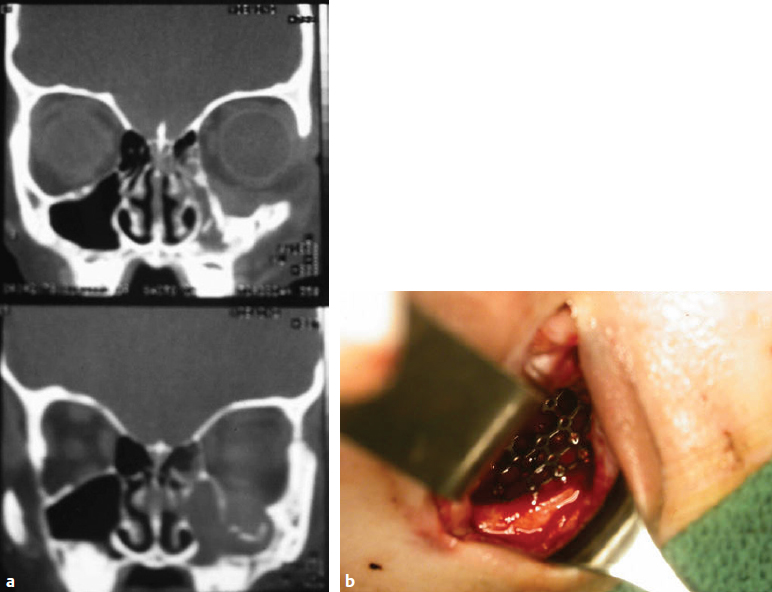

CHAPTER Pediatric facial fractures are relatively rare compared with adult injuries. The proportions and mechanical properties of the growing facial skeleton protect children from craniofacial fractures, and the watchful eye of parents decreases occurrence in early life. Because of their infrequency, large long-term clinical studies are not available to assess management and evidence-based outcomes. Despite the lack of standard treatment guidelines, outcomes are generally reported to be acceptable, owing to the resiliency of the growing craniofacial region. Nevertheless, those that do occur can be a clinical challenge to correct. Comprehensive understanding of the most significant complications will guide the surgeon in appropriate management of these patients. This chapter reviews the complications and untoward results of maxillofacial injuries in children, their avoidance, and their treatment. The pediatric skull consists of a relatively large neurocranium and a small viscerocranium. This ratio begins at 8:1 at birth but diminishes to 2:1 by adulthood. Differential growth increases the length and projection of facial structures compared with the cranial vault during postnatal development. Pediatric bone is soft and pliable. It develops adult quality as it increases in cancellous bone content. These general changes along with specific anatomic changes account for the unique nature of pediatric facial fractures and their outcomes. The frontal sinus is absent at birth. Frontal bone pneumatization begins at age 3 years and reaches the nasion by age 4 years. The frontal sinus is only pea-sized by age 7 years. Full adult size and conformation is not reached until age 15 to 19 years.1 The maxillary sinus also starts as a bud at birth. By age 7 years the maxillary sinus has extended laterally to the midpupillary line. Growth continues as permanent dentition erupts. The pediatric nose possesses several unique traits compared with an adult. The growing nose is less projected. The nasal framework is more cartilaginous and the nasal bone suture is open. Nasal growth is biphasic. The first growth phase occurs between ages 2 and 5 years, and the second occurs during puberty.2 Most nasal growth is completed by age 16 years for young women. Growth may continue beyond age 18 years for young men.3 Most of the development of the mandible derives from growth at the condyle and ramus.4 Tooth eruption and development of the alveolar process also contributes to mandible maturation. The body and symphysis remain relatively unchanged. Deciduous tooth eruption begins at approximately 6 months. It is complete at 2 years. Exfoliation begins around 6 years through root resorption. Concurrently, eruption of permanent dentition begins and continues through age 12 years. Incisors erupt around age 6 years, and canines around age 9 years. Wisdom teeth usually erupt in early adulthood.5 During the transition through mixed dentition, there is relatively low bone stock. Permanent tooth follicles occupy a large portion of mandibular volume. Between 6 and 15% of all facial fractures occur in pediatric patients.6,7 The incidence is lowest for patients age 0 to 5 years (0–1% of all facial fractures) and increases thereafter.6,8–15 Sex distribution, male to female, is 1.7:3.1.8,9,16 • Nasal bones: 5–59% • Mandible: 17–87% • Dentoalveolar: 8–32% • Maxilla: 3–16% • Zygoma: 3–25% • Naso-orbital-ethmoid: 1–8% • Frontal bone: 1–5% • Orbital: 7–41% The causes of pediatric fractures are diverse. Between 10 and 38% of fractures are caused by falls, and 27 to 34% by play accidents. Between 17 and 54% are by motor vehicle accidents, 1 to 21% are by sporting injuries, and 3 to 48% are caused by assault.7–10,17–19 Though rare, there have been a few documented cases of facial fracture from traumatic birth.9,16,18,20 Fracture distribution is unique compared with adult facial fractures7–10,16–19,21–27 (Box 49.1). Associated injuries are more common in pediatric maxillofacial trauma than in adult cases. Depending on the case series, 36 to 89% of patients experience other injuries concurrent with facial fractures6,7,9,16,19: • Soft tissue lacerations: 14 to 88% • Extremity injuries: 2 to 70% • Head trauma: 4 to 80% • Facial nerve palsy: 1% • Abdominal trauma: 1 to 18% • Cervical spine trauma: 1 to 2% • Globe trauma: 1 to 8%7,9,19,20,22 Overall complication rates range from 12 to 26%.9,18,22 Details regarding specific complications are reviewed later in this chapter. As in any trauma case, surgeons must follow proper protocol in the management of the airway, breathing, and circulation A primary survey will prompt the surgeon to secure the airway. Pediatric patients, especially younger ones, require greater attention because of the size and position of the larynx. The secondary survey includes examination of the head and neck for cranial nerve and ocular function, skeletal stability, and any sources of hemorrhage. Appropriate imaging of the facial skeleton and cervical spine, as prompted by physical examination, will assist in determining the presence and extent of fractures. Once the patient’s age, severity of injury, and presence of concurrent injuries have been accounted for, specific treatment planning for facial fractures can be initiated. Intracranial injury associated with facial bone fractures occurs at a relatively high frequency in the pediatric age group. Lack of paranasal sinus development in children may contribute to forces being transmitted to the cranium and its contents.28 As such, computed tomography (CT) is indicated to evaluate the status of the cranium and underlying intracranial contents. Injuries requiring neurosurgical intervention may require craniotomy, craniectomy, or repair of dural tears. If the frontal sinus is present and involved, it must be managed accordingly. Patients with facial fractures and associated cranial or skull base injury are at risk for further complications.29 Structural deformity, olfactory nerve dysfunction, and surgical-site infection may occur. Ophthalmic complications, such as ptosis, visual field disturbances including blindness, diplopia, telecanthus, or enophthalmos are potential sequelae. Persistent cerebrospinal fluid (CSF) leakage may result as well. Prolonged neurological deficits and posttraumatic hypopituitarism are further sequelae that warrant extended follow-up and observation. Fourteen percent of naso-orbital-ethmoidal (NOE) fractures are associated with CSF rhinorrhea.14,25 Between 70 and 85% of traumatic CSF leaks resolve within 1 week.30,31 If CSF leak persists beyond 1 week, placement of a lumbar drain usually satisfactorily decompresses the site of leakage. This allows for dural tear closure. If the lumbar drain fails to resolve the CSF leak, neurosurgical repair of the skull base defect should be performed. Unrecognized CSF leak or fistula may progress to meningitis, encephalitis, or even brain abscess. Injury to the contents of the superior orbital fissure and the optic canal is usually secondary to a skull base or orbital roof fracture. Prompt diagnosis by cranial nerve and ophthalmologic evaluation is vital to prevent a permanent visual disturbance and blindness. Because significant energy is required to cause a pediatric facial fracture, there must be a high level of suspicion for cervical spine injury. Examination during the secondary survey and appropriate CT studies may assist in the diagnosis. When injury is suspected, the cervical spine must be immobilized until definitive examination can be performed. The overall incidence of soft tissue injury with pediatric facial trauma is 14 to 42%.9,32 Severe injuries may result in a soft tissue defect from avulsion. Between 1 and 56% of cases have a significant soft tissue defect.9,33,34 Suboptimal long-term outcomes in the appearance of these scars has been reported at 6.5%.35 As in other laceration repairs, the surgeon should monitor wounds for hypertrophic scars. Revision techniques include steroid injection, laser therapy, scar revision, and reorientation of scar via z-plasty or geometric broken lines. Summary Box Unfavorable Results and Complications in Pediatric Facial Trauma Repair • Postoperative facial fracture repair • Upper third of the face • Middle third of the face • Nasal and septal fractures • Dentoalveolar and mandible fractures Complications of bony healing are relatively rare in pediatric facial fractures. They are usually associated with comminuted fractures.36 A growing facial skeleton heals faster than that of an adult.37 Furthermore, few fractures are comminuted or significantly displaced, facilitating appropriate reduction. Infection may occur and osteomyelitis can occur at any fracture site. Overall incidence ranges from 8 to 9%.9 Four percent of cases are complicated by malunion.9 Early definitive treatment and appropriate surgical technique will minimize cases of infection. If hardware is present and infection persists, eventual removal may be necessary. Research in cleft lip and palate repair has demonstrated an association with wide subperiosteal undermining and potential future adverse alterations in bony growth.38 Al though this study has not been extended to the repair of maxillofacial fractures in the growing skeleton, minimizing periosteal elevation in fracture repair is prudent for preserving normal craniofacial growth patterns. The role of rigid fixation in the development of a cranio-facial growth disturbance remains controversial. In animal studies, both wire and compression plate fixation of the craniofacial skeleton have resulted in growth alterations.39–41 These studies involved disruption of the coronal suture line as well. No animal models have investigated removal of hardware or wiring and the subsequent growth patterns. Furthermore, no studies exist that examine changes in the growing mandible, the most common site undergoing open reduction for trauma. Regardless, there are several case reports detailing migration of retained fixation hardware during growth.42–45 Some case series have reported intracranial migration of hardware and association with injury to the globe, seizure activity, meningitis, and damage to underlying cortex.46,47 Because of the risk of growth disturbance and hardware migration, some have advocated resorbable hardware. Resorbable plates are typically manufactured as a blend of materials. Poly-L-lactic acid (PLLA) maintains its strength for up to 6 months. It is less malleable than other resorbable materials. Polyglycolic acid, poly-DL-lactic acid, and polydioxanone are weaker but more malleable. Current resorbable plates are typically composed of a blend of PLLA and one of the other materials to achieve desirable physical characteristics. All resorbable plates are mechanically weaker than titanium fixation plates. To circumvent this, resorbable plates are usually larger in profile. Manufacturers effectively exchange strength and low profile for resorbability. Some cases of device extrusion and sterile abscesses have been reported.48 In their series of 1,884 pediatric craniofacial patients, Eppley et al49 reported outcomes in patients treated with resorbable poly-L-lactic-polyglycolic acid (PLLA-PGA) plates. There were five cases of resorbable device failure requiring reoperation. Failure was the result of plate fracture rather than screw pullout. Twelve patients suffered from foreign body reaction presenting at 4 to 10 months after surgery. Imola et al48 published a case series of 57 patients treated with resorbable plates, 11 of whom underwent facial fracture repair. Two of three mandibular fracture cases experienced delayed union. One of those two patients required revision surgery via metal plate fixation because of plate extrusion and surgical site infection. With continued improvement in biomaterial technology, more recent case series have reported few complications with resorbable plates for mandible fractures.50–52 These included infection requiring removal of hardware (1 of 22 patients). Although uncommon in adults, superior orbital fractures are more common than floor fractures in children younger than age 7 years.25 This is most likely related to the timing of the development of the frontal and maxillary sinuses. As such, supero-orbital fractures are more likely to be associated with a dural tear. They are at risk for progressive diastasis of the fracture line. Although only 0.03 to 2.2% of all pediatric skull fractures result in growing skull fractures, 90% occur in patients younger than 3 years. Fifty percent occur in those younger than 1 year.53–57 Younger children are susceptible because of their malleable cranial vault and rapidly growing brain.53,58,59 The presence of a dural tear at the time of injury seems to be necessary for the development of a growing skull fracture.58,60–63 Typically, the scalp is intact. A collection of CSF at the fracture site (cephalhydrocele) indicates the dural tear. Other presenting symptoms may include diplopia, proptosis with or without pulsatility, eyelid edema, or orbital asymmetry. Patients may present 2 to 18 months after injury.64 Without proper recognition and treatment, the skull fracture will continue to expand with destruction of the bony vault, porencephalic cyst, epilepsy, paresis, cerebral scarring, brain atrophy, and cerebral herniation.63,65,66 A significant mass effect on the orbit may result in optic nerve compression.67 Prompt diagnosis and treatment of a dural tear associated with a fracture is vital to avoid a growing fracture. If the injury has already progressed to a growing skull fracture, surgical treatment with wide exposure using a coronal incision is advocated. Dural edges are usually retracted at the time of repair.66,68 Havlik et al66 recommend for mal craniotomy with removal of meningovascular cicatrix; drainage of cystic structures; dural repair, which may require grafting; and reconstruction of the cranial vault. Rongeuring bone rather than performing a craniotomy will result in loss of bone stock. This makes healing difficult. Bone grafting of the anterior skull base or orbital roof may be indicated. Patients may require secondary procedures for persistent orbital asymmetry.57 Mucoceles are the result of fractures involving the frontal sinus associated with mucosal tear.69 Mucosa entrapped in a fracture line may result in cyst formation. Growing mucoceles produce several inflammatory cytokines, such as prostaglandin and collagenase. These can erode surrounding bone.70,71 Mucocele development occurs over a span of years. They are only likely to present in adulthood.72 Furthermore, mucoceles originating from trauma in childhood are rare, given that the frontal sinus is not present before age 4 years and is not fully developed until adulthood.1 Treatment of a mucocele remains controversial. Integrity of the posterior table, dura, frontal recess, and any other bony defects must be assessed. All diseased mucosa must be removed. If the frontal recess is patent and functional, then the frontal sinus may be left intact. Otherwise, obliteration or cranialization with occlusion of the frontal recess is indicated. Orbital roof or frontal bone defects should be reconstructed as needed. NOE fractures are the major cause of telecanthus in pediatric facial trauma. Comminuted NOE fractures usually require transnasal fixation to properly reposition the medial canthal tendon. A drill hole is placed posterior to the lacrimal fossa and linked to the fragment containing the medial canthal tendon with a small-gauge wire.73 This technique usually provides an anatomical reduction of the fracture. Alternatively, permanent sutures anchored to a miniplate can achieve the same result. Regardless of the technique used, anatomical repositioning requires satisfactory superior and posterior positioning of the canthal remnant. Residual telecanthus may nevertheless result even after satisfactory initial treatment. In Singh and Bartlett’s series74 of 20 pediatric patients with NOE fractures, 6 required further canthal repositioning. Any fracture involving the orbital floor may cause entrapment of orbital contents. Trimalar, Le Fort, and simple floor fractures are all susceptible. Pure orbital wall fractures are more common in children than adults because of their incomplete pneumatization of the paranasal sinuses. As stated previously, children older than 7 years are more likely to experience floor fractures, whereas those younger than 7 years are more susceptible to pure orbital roof fractures. Furthermore, because most pediatric facial fractures occur after the age of 5 years, most simple orbital fractures in children involve the floor.75,76 Orbital floor fractures are typically classified as “direct,” involving a direct impact to the orbital rim with subsequent fracture of both the inferior orbital rim and the orbital floor, or “indirect,” consisting of a force impacting the orbital contents and causing them to break through the weakest point of the orbital walls. In the pneumatized maxilla, this is the orbital floor. Because of the propensity of pediatric bone to greenstick fracture, entrapment is significantly more common in children.77 Patients with entrapment may present with symptoms of oculocardiac reflex: bradycardia, nausea, and syncope.78 Surgeons should nevertheless perform forced duction testing at the time of injury to rule out entrapment even if symptoms are absent. Children may present without any associated findings. This has been termed “white-eyed” blowout.79 Patients without entrapment can be observed for enophthalmos and diplopia during the days after injury. Entrapment can also occur during surgical repair of an orbital floor fracture. Before closure during orbital floor reconstruction, the surgeon should repeat forced duction testing to rule out entrapment of orbital contents. Although inferior rectus entrapment with symptoms of oculocardiac reflex is considered a surgical emergency, the timing of orbital floor repair with asymptomatic entrapment remains unsettled. Some authors advocate treatment within 1 or 2 days.77,79,80 Prolonged entrapment may predispose the inferior rectus to ischemic contracture and necrosis.81 Fibrosis and adhesions of intraorbital contents may also be a causative factor of ocular restriction.82 Furthermore, some studies have shown that most cases have no muscle within the entrapped contents.83,84 Regardless of the cause, no definitive treatment protocol currently exists. Cases of restricted movement with onset as early as 72 hours after injury have been documented.78 Conversely, some evidence suggests that immediate repair is not necessary. Egbert et al85 reported a case series of 34 patients. They reported no difference in mobility or diplopia for children treated within 1 month of fracture. However, patients receiving therapy within 7 days had a more rapid improvement in symptoms than those treated later. They recommended early treatment for patients with severe symptoms of entrapment. Data regarding long-term outcomes and complications of surgical intervention in pediatric floor fractures are lacking. Nevertheless, surgeons typically advocate surgical approaches that allow for adequate exposure and proper implant placement. A transconjunctival approach allows for a “scarless” surgery but has limited exposure compared with external approaches. Lateral canthotomy can improve exposure, but the surgeon must repair the canthal ligament before case completion. “Middle lamella” syndrome, violation and subsequent scarring of the orbital septum with resultant lower lid malpositioning, has not been investigated in detail in the pediatric literature. Measures should be taken to avoid its occurrence. In the external approach or the preseptal subconjunctival approach, surgeons should incise the orbital septum below the orbital rim to allow for appropriate graft coverage and suture reapproximation. Nonresorbable alloplastic implants are at risk for migration in the growing orbit and should be avoided. They may impinge on orbital structures and adversely affect movement. Infection is also an increased risk. It is treated with implant removal. In the case of supramid, the foreign body capsule should be marsupialized into the maxillary sinus, because spontaneous hemorrhage has been reported.86 Persistent diplopia after orbital trauma may also result from transient muscle ischemia with subsequent strength imbalance. Injury to cranial nerves III, IV, or VI may also negatively affect ocular motility. Any suspected impingement should be evaluated and imaged as necessary. In cases of muscular imbalance, prism glasses can be used for conservative management. More aggressive therapies include botulinum toxin injections into restricted extraocular muscles or strabismus surgery to address muscle length.87 Either a pure orbital floor fracture or a zygomaticomaxillary complex fracture involving the orbital floor will result in enophthalmos if the floor defect is not properly assessed and corrected (Fig. 49.1). Most surgeons recommend a period of observation to allow for resolution of periorbital edema to ascertain true extent of enophthalmos. Losee et al76 examined their series of patients with orbital fractures and the outcomes with conservative management. Three of ten pure orbital fractures managed conservatively had detectable enophthalmos. These patients had higher energy impact trauma, larger fracture widths, greater fracture area, displacement, and soft tissue herniation. None of the patients with enophthalmos demonstrated any functional deficit. Degree of enophthalmos for all three patients measured no more than 1 mm. These findings suggest that conservative management of pediatric enophthalmos without further complication of dystopia or entrapment may be considered. This may be related to the elasticity of the orbital connective tissue in a child and the ability of their periosteum to resist tearing.26,76 However, some cases do require secondary surgery. In their review of complex orbital fractures, Nowinski et al88 documented 3 of 14 patients with persistent enophthalmos or ocular dystopia requiring surgical revision. Fig. 49.1 A pediatric patient after an orbital blowout fracture. (a) Radiological findings of the floor blowout, with herniation of the orbital contents into the maxillary sinus and a “greenstick” fracture of the floor. (b) The intraoperative view of the placement of an orbital floor implant via a transconjunctival approach. Accurate incidence of nasal fractures has been difficult to ascertain. Many are managed in an outpatient setting. Inpatient statistical analysis may therefore omit many cases. Regardless, most authors regard the nose as the most common site of pediatric facial fractures.8,9,16–19,21–23,89 Several nasal fracture classification schema exist. Moran90 specifically described patterns seen in children. Lateral fractures are the most common. These involve ipsilateral infracture and contralateral outfracture of the junction of the ascending process of the maxilla and the nasal bone. Linear fractures are nondisplaced and without comminution. Frontal fractures, like those in adults, are more likely to cause greater trauma. Vector of force may transmit injury posteriorly to the lacrimal and ethmoid bones, or posterior telescoping of the nasal tip or pyriform aperture may occur. “Open book” fracture is a type of frontal fracture particular to the pediatric population related to incomplete nasal bone fusion. Nasal bones separate at the midline, causing central depression and lateral flaring and displacement over the frontal process of the maxilla. Verwoerd and Verwoerd-Verhoef2 described common patterns of pediatric nasal septal fractures. Vertical fractures involve fractures caudal to the insertion of the upper lateral cartilages and extend to the anterior nasal spine. Left untreated, they will result in deviation of the caudal septum and nasal tip. A “C-formed fracture” extends posteriorly and superiorly from the central cartilaginous septum to the perpendicular plate. These fractures result in both bony and cartilaginous septal deviation. Recognition of these fracture patterns during physical examination will assist the surgeon in performing the appropriate treatment and reduction maneuvers in these patients. This requires both external and internal nasal examination. External examination should focus on inspection of the deformity and palpation of crepitus, mobility, and step-offs. Proper instrumentation is paramount to complete intranasal examination and will allow the surgeon to evaluate the presence of a septal hematoma, septal fracture or deviation, epistaxis, intranasal lacerations, and patency of the internal nasal valve. Headlight illumination, suction, topical decongestants, and a nasal speculum are all necessary for adequate exposure and examination. Researchers have postulated two models of nasal growth and development. According to Verwoerd and Verwoerd-Verhoef’s model,2 two growth centers exist in the nose. The sphenodorsal zone extends from the sphenoid to the nasal dorsum and results in increased length and height of the nasal dorsum. The keystone area, the junction of the upper lateral cartilages and the nasal septum at the bony–cartilaginous interface, is part of this growth zone. The sphenospinal zone extends from the sphenoid to the anterior nasal spine and results in increased projection of the nose and maxilla. Injury to either growth center may result in progressive deformity in the dimensions each growth center controls. Another model describes a two-phase growth of the premaxilla.91 In this model, the septo-premaxillary ligament transmits an inferior and anterior force from the growing nasal septum to the premaxilla until the maxillae reach their definitive boundaries. A second phase of growth then occurs, intrinsic to the orbital and posterior surfaces of the maxillae. Saddle nose deformity of the nasal dorsum (Fig. 49.2), widening of the nasal bridge, widening of the nasal base, decreased nasal length, and decreased projection are all possible sequelae in patients even after satisfactory surgical treatment of a nasal fracture.92,93 Because the nose continues to grow into late adolescence or even adulthood for men, most surgeons recommend a conservative approach to the management of nasal fractures. Furthermore, the younger the patient at the time of injury, the more likely long-term deformities will occur. Although cases of nasal trauma at birth may resolve with no intervention, some authors advocate immediate treatment regardless of nasal airway patency.94,95 They propose that the ease and safety of the maneuver weighed against the risk of functional and developmental abnormality justifies intervention. Otherwise, pediatric nasal fractures should be treated within 3 to 5 days after injury. Bony healing is more rapid than that of adults.96 Closed reduction under anesthesia permits proper examination, reduction, and splinting of the fracture. Older children may tolerate treatment with regional nerve blocks. In cases of severe nasal obstruction, some surgeons recommend open septorhinoplasty.97–101 Care must be taken to avoid the aforementioned growth centers whenever possible. Resection of septal cartilage should always be minimal, unless septal deflection is the major contributor to airway obstruction. Bony and cartilaginous septal continuity should be maintained. Resected cartilage should be recontoured and replaced. Surgeons may opt to use polydiaxone scaffolding to support the regrafted cartilage. Animal studies have demonstrated normal cartilage growth after a cartilage defect has been bridged with polydiaxone.102 Spreader grafts should be avoided. They disrupt the dorsoseptal growth center. Crushed cartilage can fill areas at risk for perforation. However, it lacks the mechanical strength to support the growing nose.103 Unfortunately, replacement of cartilage does not guarantee normal nasal growth after repair. Several case series have reported deformities and growth disturbances that have arisen years after surgical treatment.104–106 This is most likely related to injury and repair occurring before the adolescent growth spurt. Reestablishing the end-to-end relationships of cartilage fragments should be the surgeon’s goal to minimize future growth disturbance. If saddle nose deformity does develop, secondary surgery is required to establish satisfactory dorsal height and length (see Fig. 49.2).